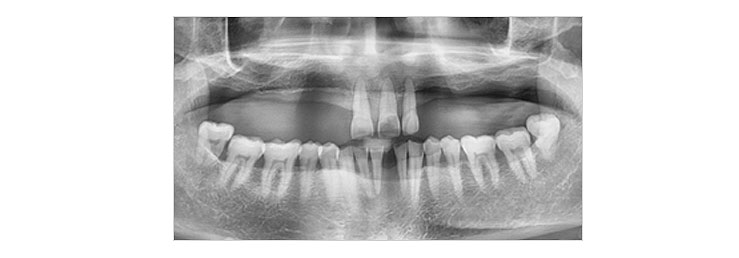

임플란트 식립

1차 수술을 통해 정확한 위치에 임플란트를 심습니다.

임플란트의 골유착 및 지대주의 연결

임플란트 수술 후 골의 치유 및 임플란트의 골유착이 진행되면 2차 수술을 통해 잇몸 밖으로 기둥(지대주)을 연결합니다.

*수술 형태에 따라 2차 수술은 생략될 수 있습니다.

보철물 장착

임플란트의 기둥(지대주)위에 인공치아를 만들어 넣는 과정입니다.